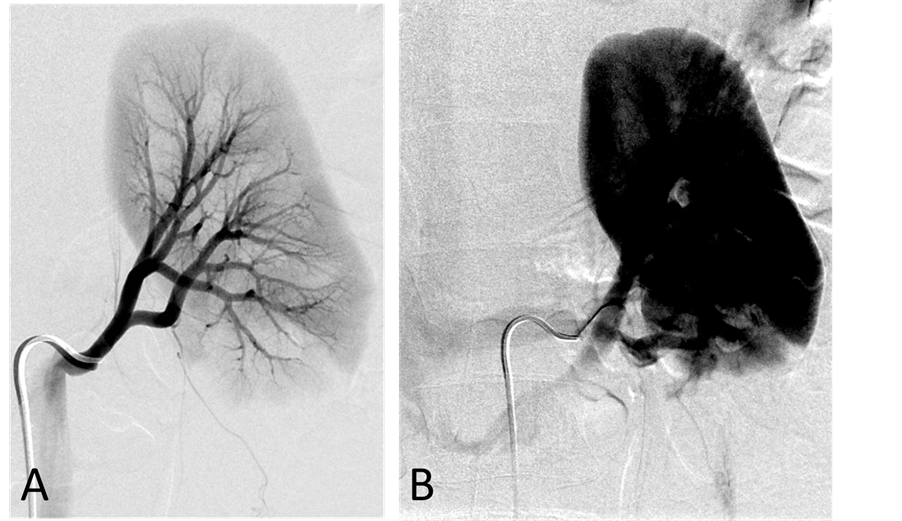

With the patient under general anesthesia, a 5-Fr Omni Flush catheter (Angio Dynamics, Queensbury, NY, USA) was placed in the aorta above the celiac axis from a percutaneous retrograde transfemoral arterial approach, and aortograms were performed, first with 30 cc of CO2 and then in the anterior-posterior (AP) and left anterior-oblique (LAO) projections with Visipaque (GE Healthcare, Cork, Ireland, UK). During each of the runs, there was a moderate increase in blood pressure from baseline systolic pressures of 120 s to 145 - 150 s, lasting 5 minutes, accompanied by bradycardia and transient arrhythmia. A nitroglycerin drip was started; however, the patient did not require any alpha or beta blockers. Next, a 5-Fr shepherd hook catheter (Angio Dynamics, Queensbury, NY, USA) was positioned and digital subtraction angiography (DSA) was performed, sequentially, in the right and left renal arteries, superior mesenteric artery, and finally the celiac axis. The aortograms revealed two vascular retroperitoneal tumors to the right and left of the aorta, at the level of L1-2, measuring 22 mm × 27 mm and 26 mm × 27 mm, respectively (Figure 2(A) and Figure 2(B)). The right retroperitoneal mass was located posteroinferior to the right renal artery and posterior to the inferior vena cava (IVC). The left retroperitoneal mass was located between the left main renal artery and the inferior accessory renal artery. The inferior accessory renal artery supplying the lower pole of left kidney showed diffuse narrowing due to either compression or catecholamine release by the tumor (Figure 3(A) and Figure 3(B)). Subsequently, bilateral renal arteriograms were performed without a hypertensive response to the injection of contrast material. The right main renal artery was displaced by the tumor with mild arterial narrowing (Figure 4(A) and Figure 4(B)). Left renal arteriogram showed a patent main renal artery with a circumaortic renal vein (Figure 5(A) and Figure 5(B)).

Figure 4. (A) Right renal arteriogram, arterial phase. There is mild compression of the main renal artery by the tumor associated with mild narrowing of the renal artery at the hilus; (B) Right renal arteriogram, capillary phase. No tumor blush is seen.

the retroperitoneal masses. The concentration of epinephrine in the IVC was normal. The values of catecholamines are shown in Table 1. Left renal vein renin value was 117.1 ng/mL/hour (n, 0.5 - 3.5 ng/mL/hour), right renal vein renin level, 75.9 ng/mL/hour, and IVC, 91.4 ng/mL/hour. The left renal: right renal renin ratio was 1.5, lateralizing renin excess to the left kidney which is most likely due to narrowing of the left inferior accessory renal artery caused by the tumor.

Figure 5. (A) Left renal arteriogram,arterial phase. The main and intrarenal arteries are patent; (B) Left renal arteriogram, capillary and venous phase. The nephrographic defect in the lower pole of the kidney is the part of the kidney supplied by the accessory renal artery arising from the aorta. There is circumaortic renal vein as renal vein variation.